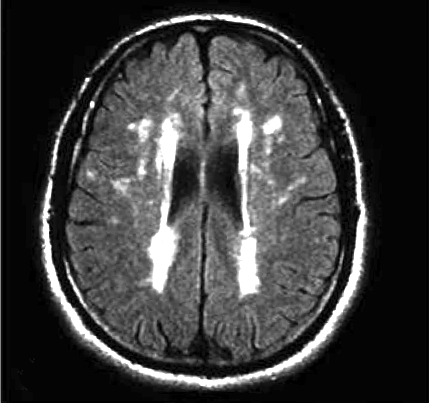

Fazekas grades. Лейкоареоз Fazekas 1 что это. Лейкоареоз степени по Fazekas. Fazekas 2. Фазекас 2 мрт.

Fazekas grades. Лейкоареоз Fazekas 1 что это. Лейкоареоз степени по Fazekas. Fazekas 2. Фазекас 2 мрт.

Fazekas grades. Fazekas степени мрт. Фазекас 2 мрт. Шкала Фазекас мрт. Лейкоареоз 3 степени по Fazekas.

Fazekas grades. Fazekas степени мрт. Фазекас 2 мрт. Шкала Фазекас мрт. Лейкоареоз 3 степени по Fazekas.

Fazekas grades. Классификация Фазекас. Fazekas мрт. Лейкоареоз степени по Fazekas. Фазекас классификация мрт.

Fazekas grades. Классификация Фазекас. Fazekas мрт. Лейкоареоз степени по Fazekas. Фазекас классификация мрт.

Fazekas grades. Фазекас классификация мрт. Лейкоареоз Fazekas 1 что это. Fazekas степени мрт. Лейкоареоз степени по Fazekas.

Fazekas grades. Фазекас классификация мрт. Лейкоареоз Fazekas 1 что это. Fazekas степени мрт. Лейкоареоз степени по Fazekas.